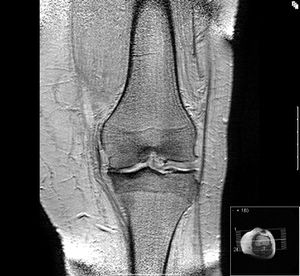

خشونة الركبة Knee osteoarthritis مرض ينتج عن تآكل الغضاريف الناعمة التي تغطي سطح المفصل والتي تساعد على نعومة الحركة. حيث يحدث ضعف في تماسك هذه الغضاريف مما يؤدي إلى تشقق سطحها ثم تتآكل تدريجياً إلى أ، يصبح سطح العظمة عارياً من الغضاريف التي تحميه. ويصاحب هذا التآكل إالتهاب في الغشاء المبطن للمفصل (الغشاء السينوفي) المسئول عن إفراز السائل الذي يساعد على تزييت سطح المفصل وهذا الإلتهاب يؤدي إلى حدوث إرتشاح (تجمع الماء) بالركبة.

ومفصل الركبة من أعقد مفاصل الجسم تركيبا، ويحتاج لمهارة معينة عند التدخل الجراحي، حيث إن آلام الركبة لا تعني بالضرورة خشونتها.. فهناك أسباب كثيرة لذلك.